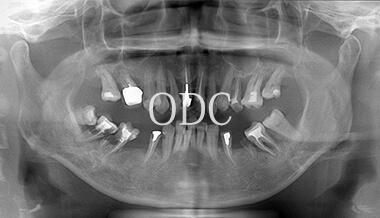

パノラマX線写真

術 前

術 後

術前・術後のパノラマX線写真です。上顎(オールオン4)は4本のインプラントにチタンフレームの上部構造が固定されているのがおわかりになると思います。下顎のインプラント埋入部位、上顎のインプラントの本数、再度写真をご覧いただくと、とてもインプラントが埋入されているとわからない程の外観、下顎の残存歯(元々の自分の歯)とも区別がつかない審美性が実現されています。